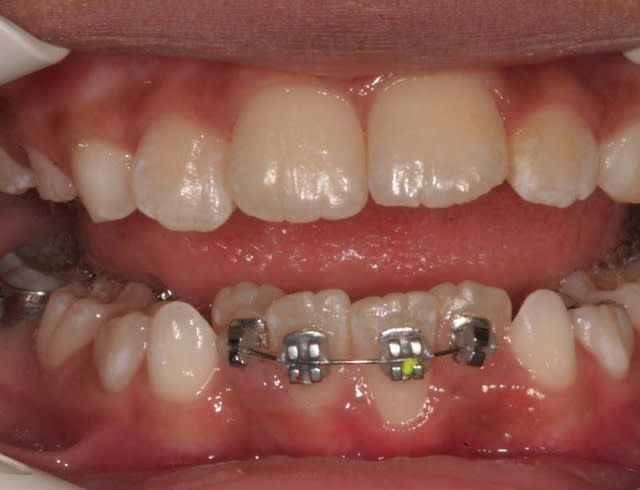

C’est un cas que j’ai traité en deux temps, interception, période d’interruption, fin de TTT.

ce n’est pas un cas trop difficile, aussi j’ai assez peu de photos

Avant TTT.

à suivre Bjc.

c'est le mm. patiente

la coloration des dents est assez remarquable

P.S.: j'avais à l'époque un Fuji mono-objectif

les photos de la contention ont été prises avec un Canon 1000 objectif Macro

les couleurs ne sont pas tout à fait les mm.

mais les dents ont gardé la mm. forme et les taches sont reconnaissables